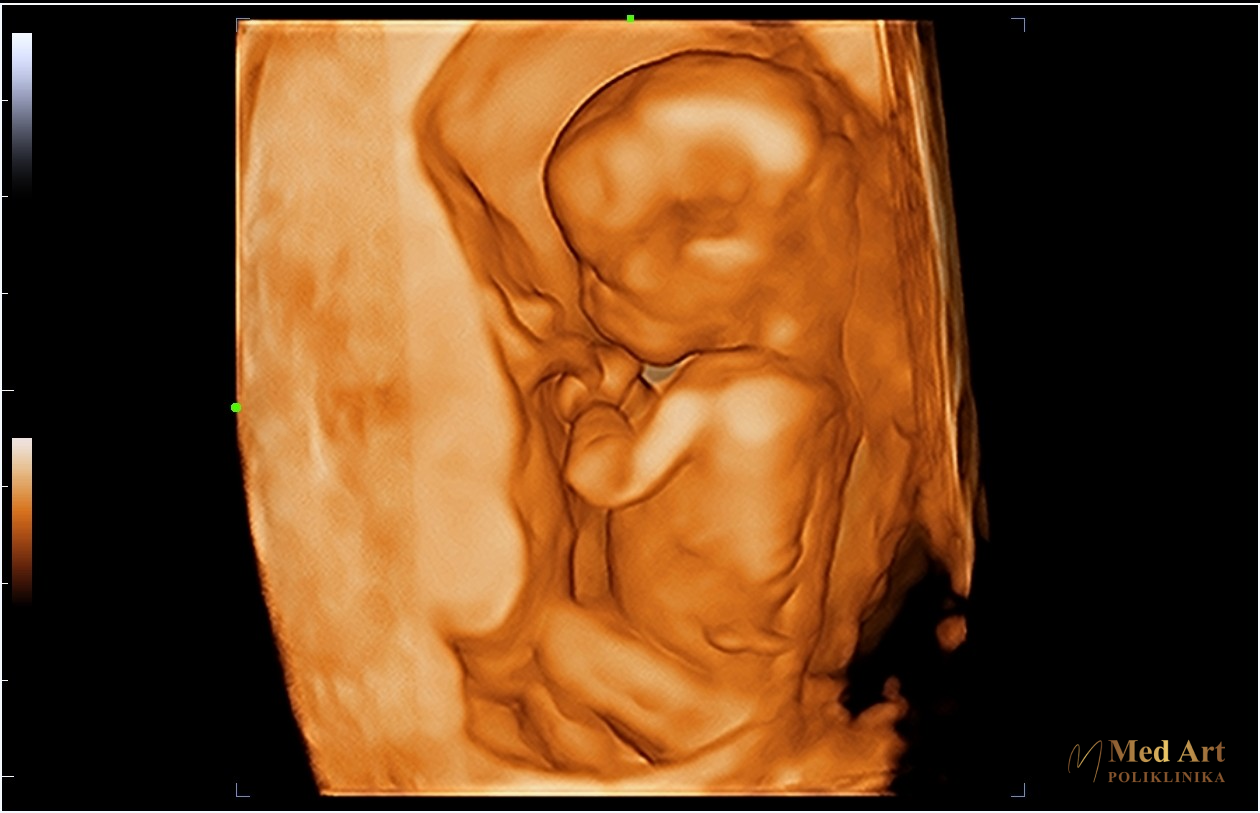

Ultrazvučni pregledi obavljaju se u različitim fazama trudnoće kako bi se pratili ključni trenuci razvoja bebe, od formiranja prvih organa i udova do kasnijih faza, kada se beba u potpunosti razvija i priprema za rođenje.

U galeriji koja slijedi, možete vidjeti ultrazvučne slike beba u 6., 7., 8., 12., 14., 20., 21., 24., 27. i 34. tjednu trudnoće, koje prikazuju njihov razvoj od rane trudnoće pa sve do priprema za dolazak na svijet.